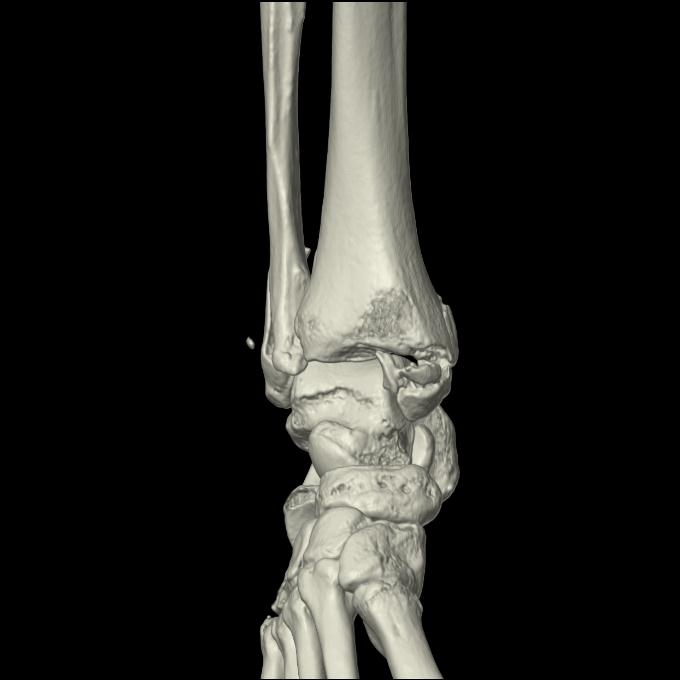

56476 8/28 4R 1/21 2R 左足関節 デジカメ写真 72歳女性 右足関節AS